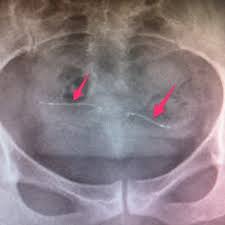

Se ha demostrado que esta técnica es efectiva para prevenir el embarazo en un 99,8% de los casos. Tras la cirugía se debe realizar una histerosalpingografía que compruebe si las trompas de Falopio han sido bloqueadas completamente, esta prueba consiste en introducir un líquido, que se puede ver con rayos X, a través del cuello uterino, de manera que pinta todo el interior uterino y, si no fuese por la ligadura de trompas, saldría a través de las trompas hacia la cavidad abdominal.